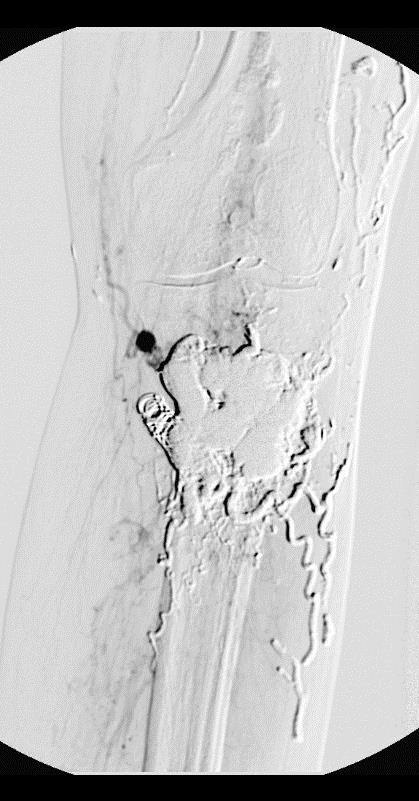

与酒精栓塞相关的心血管衰竭(Cardiovascular Collapse)是非常危险的并发症。文献上已经报告7例。其中2例动静脉畸形,5例静脉畸形。所有病例接受少于0.8ml/kg的无水酒精(范围0.3~0.8ml/kg;平均0.5ml/kg)。4例复苏,3例死亡。所有7例未发现肺动脉栓塞[3]。 如何预防无水酒精相关疾病引起的心血管衰竭? 无水乙醇栓塞导致心血管衰竭一个普遍认为的原因是肺动脉痉挛。酒精的注射最大总量为0.5-1ml/kg;每次注射0.1ml/kg;每次注射间隔为5-10分钟。补液和利尿;无水酒精的流出控制,包括止血带和酒囊导管。注射酒精是进行肺动脉压力的监测。 栓塞材料相关并发症 NBCA:导管粘连;硬块形成(hard mass formation);皮肤和粘膜渗出。 微球或PVA:远端动脉或肺动脉栓塞 弹簧栓子:近端栓塞

作为介入放射科医生要求了解栓塞和硬化的危险和获益,确保减少并发症的情况下病人最好获益。 二、静脉畸形硬化并发症 栓塞剂外溢